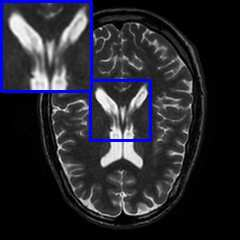

Limited by imaging systems, the reconstruction of Magnetic Resonance Imaging (MRI) images from partial measurement is essential to medical imaging research. Benefiting from the diverse and complementary information of multi-contrast MR images in different imaging modalities, multi-contrast Super-Resolution (SR) reconstruction is promising to yield SR images with higher quality. In the medical scenario, to fully visualize the lesion, radiologists are accustomed to zooming the MR images at arbitrary scales rather than using a fixed scale, as used by most MRI SR methods. In addition, existing multi-contrast MRI SR methods often require a fixed resolution for the reference image, which makes acquiring reference images difficult and imposes limitations on arbitrary scale SR tasks. To address these issues, we proposed an implicit neural representations based dual-arbitrary multi-contrast MRI super-resolution method, called Dual-ArbNet. First, we decouple the resolution of the target and reference images by a feature encoder, enabling the network to input target and reference images at arbitrary scales. Then, an implicit fusion decoder fuses the multi-contrast features and uses an Implicit Decoding Function~(IDF) to obtain the final MRI SR results. Furthermore, we introduce a curriculum learning strategy to train our network, which improves the generalization and performance of our Dual-ArbNet. Extensive experiments in two public MRI datasets demonstrate that our method outperforms state-of-the-art approaches under different scale factors and has great potential in clinical practice.